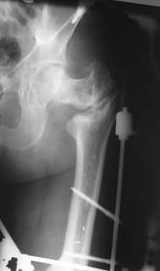

В приложении пример пациента, близкого по картине к тому, что представил Виктор (варус и смещение периферического отломка на поперечник кзади). Сделали как раз то, что Виктор исходно намеревался - аппаратная коррекция и затем гамма.

По опыту подобных случаев, аппарат лучше на бедро, без таза пока. В проксимальный фрагмент 3 стержня по оси шейки. Дистальный - хватит 1 стержня или 2 спиц в дистальном метафизе и 1 стержня вверху. Если планируете гвоздь, надо с гиперкоррекцией восстановить длину и ось, т.е. вальгизировать проксимальный отдел. При наложении аппарата сделать остеоклазию, добиться уверенной подвижности. Регенерат не нужен, тяните на пределе переносимости пациентом - хоть 2 см/сут. Обычно меньше.

Второй этап - на следующий день после окончания коррекции.

Если все получилось, т.е. закрыто сопоставить с гиперкоррекцией, накладываете дистрактор таз-бедро или используете тракционный стол, и гвоздь можно делать закрыто. Пластика то есть не нужна. Если клинковая пластина - может получиться как при меежвертельной остеотомии, боковая компрессия by mismatch. Тогда тоже пластика не нужна. Если не получатся, можно и сделать.